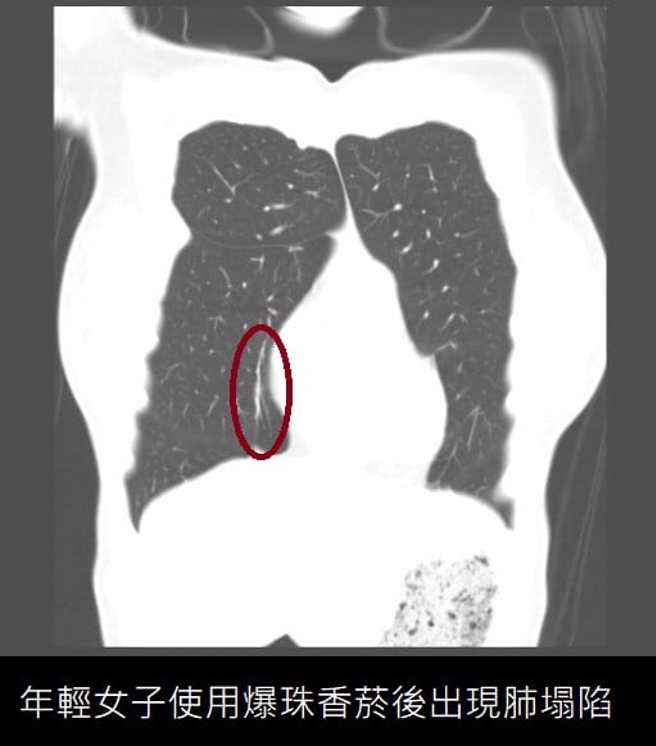

蘇一峰表示,這名年輕女子使用爆珠香菸後就一直咳,因此到醫院看診。他幫女子照電腦斷層,「慘了....發現肺爆炸了!肺塌陷了!」他解釋,爆珠香菸有香水珠,抽菸前若先壓破就可吸到香菸味,「結果爆珠香菸讓肺爆了。」

蘇一峰曾表示,肺塌陷不只會造成肺部的反覆感染、引發成重症,更可能長期損害肺功能,造成肺活量的下降。肺塌陷目前也無沒有好的治療藥物,因此呼籲民眾要小心注意遠離電子煙的傷害,避免一輩子的肺部傷害。